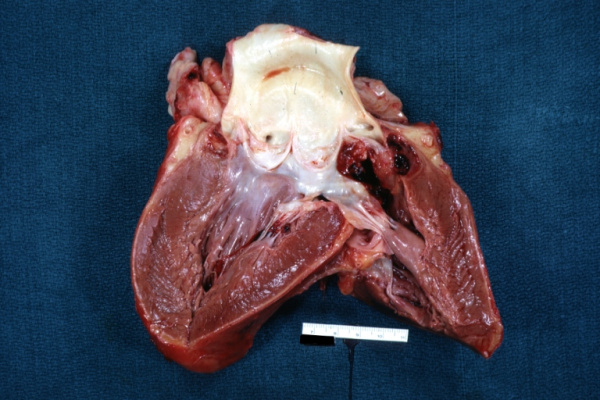

При ревизии мы установили, что створки двустворчатого АК представлены неподвижными сросшимися между собой конгломератами кальция с резким сужением эффективной площади отверстия клапана. Выраженный кальциноз отмечен вокруг аорто-правожелудочковой фистулы размером 2,0×3,0 см, располагающейся над устьем правой коронарной артерии. После иссечения створок АК и тщательной декальцинации, в том числе краев аорто-правожелудочкового дефекта, мы выполнили пластику последнего ксеноперикардиальной заплатой со стороны аорты, стенки фистулы остались интактными. Далее последовательно осуществили протезирование АК механическим протезом, ушивание аорты. Операцию заканчивали стандартно.